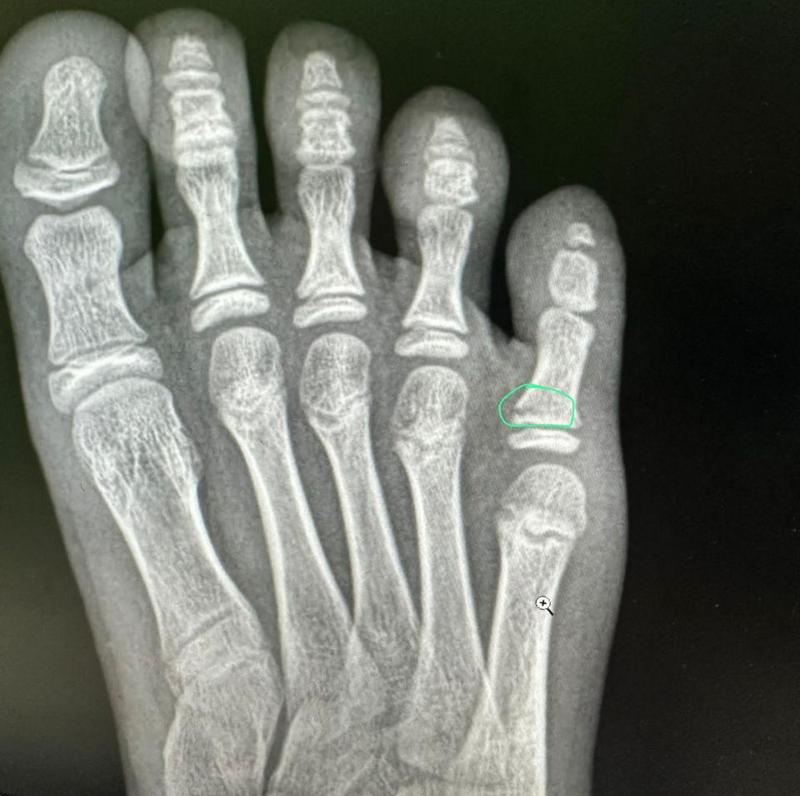

Ребёнка доставили в травмпункт, где диагностировали перелом пятого пальца стопы. На ногу был наложен гипс.